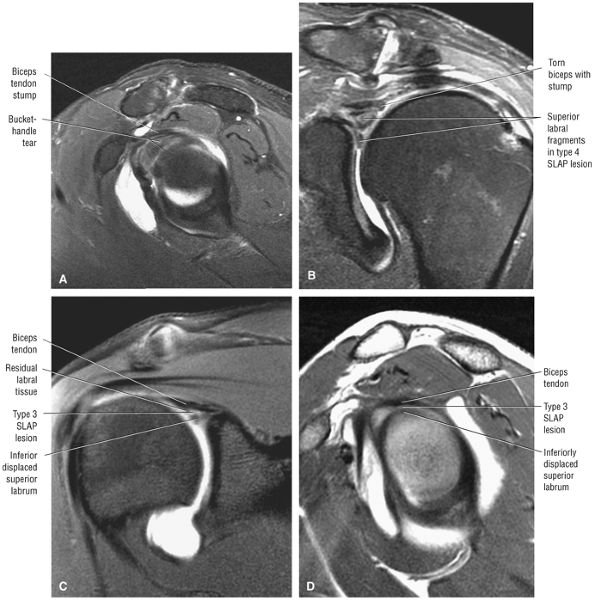

The SLAC lesion is combined with the anterior component of a SLAP 2 tear.

-

The SLAC lesion is a type of instability and not an impingement lesion.

![]() |

|

FIGURE 8.178 ● Potential sites of involvement in microinstability, including the anterior supraspinatus and anterior component of a SLAP 2 in the SLAC lesion; the posterior cuff and posterior component of a SLAP 2 in the posterior peel-back lesion; the classic anterior-to-posterior SLAP 2 lesion; anterosuperior impingement (ASI) involving the superior subscapularis, CHL–SGHL complex, the anterior supraspinatus and anterosuperior labrum, and the middle glenohumeral ligament (MGL) in anterior laxity.